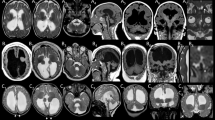

Since in utero electroporation results showed a major effect of disease-causing TUBG1 variants on neuronal migration, we first investigated whether Tubg1Y92C/+ mice display layering anomalies at embryonic stages. We analyzed thickness of the CP and different layers by immunohistochemistry on E18.5 brains (Fig. 5a). While we observed no difference in total CP thickness between the WT and Tubg1Y92C/+ mice, a more detailed analysis revealed an increase in layer V thickness with a concomitant reduction of layer VI in Tubg1Y92C/+ mice. Additionally, CTIP2 staining showed that Tubg1Y92C/+ mice present with visibly abnormal organization of layer V, which is larger and with lower cell density, while it presents with a more compact organization in control mice. On the other hand, we also observed a small population of heterotopic SATB2+ cells at the interphase of the IZ and the CP of mutant embryos (Fig. 5b). Given this observation, we assessed neuronal migration by labelling a cohort of progenitors with EdU at E14.5 and examining their localization four days after in the SVZ/VZ, the IZ and in the six layers of the CP that we divided in five equal bins (Fig. 5c). We observed a higher percentage of EdU-positive cells in the IZ at the limit with layer VI with a corresponding depletion of cells in bins 3, 4, and 5 of the CP (Fig. 5d). Arrested cells appeared as a visible band in section images and were positive for SATB2 (Fig. 5e), consistent with our previous observations.

Tubg1Y92C/+ mice show abnormal cortical layering during development. a E18.5 cortices stained against SATB2 (gray), CTIP2 (magenta) and DAPI (blue). Vertical lines depict how cortical layers were considered for quantification, scale bar 50 µm. b Histograms represent the thickness of the cortical layers and CP (upper panel) and the cell density of layer V (lower panel). Data are from at least five embryos per condition, unpaired t-test, *p < 0.05, **p < 0.01. Right image shows heterotopic SATB2+ cells. Scale bar 50 µm. c EdU staining in the cortex. Cortical plate was divided into five equal bins from the intermediate zone to the marginal zone. White arrows show EdU-positives cells accumulation in the IZ. CP, cortical plate; IZ, intermediate zone; VZ/SVZ, ventricular zone/subventricular zone. Scale bar 100 µm. d Quantification of EdU-positive cells in the specified regions, n = 3 embryos per group, Two-way ANOVA with Tukey’s multiple comparisons test, *p < 0.05, ***p < 0.001. e Representative image of SATB2 staining in cortices of EdU injected Tubg1Y92C/+ mice. Scale bar 50 µm. f Locomotory paths (colored lines) of electroporated neurons during time-lapse imaging. Scale bar 50 µm. g Percentage migrating neurons, n = 3 WT and n = 4 Tubg1Y92C/+; h average migration velocity, i average number of pauses, and j. total time spent in pause, during the 10 h of recording, n = 4 independent experiments per group. Unpaired t-test, **p < 0.01, ***p < 0.001 compared to wild type mice. k Percentage electroporated bipolar cells persisting bipolar or transitioning to multipolar morphology in 10 h recordings (n = 3 WT, n = 4 Tubg1Y92C/+ independent experiments per group). l Percentage electroporated multipolar cells persisting multipolar or transitioning to bipolar morphology in 10 h recordings (n = 3 WT, n = 4 Tubg1Y92C/+, independent experiments per group). m Percentage of arrested electroporated bipolar neurons with the centrosome ahead of nucleus, n = 3 WT, n = 4 Tubg1Y92C/+ independent experiments per group. Unpaired t-test, ***p < 0.001 compared to wild type mice. All data are presented as mean ± s.e.m. Source data are provided in the Source Data file

Using a recently developed robust approach for the assessment of 166 brain parameters across 22 distinct brain regions27 (Supplementary Dataset 1), we analyzed neuroanatomy in 16-weeks-old male Tubg1Y92C/+ mice by systematically quantifying the same sagittal brain region at Lateral + 0.60 mm. Overall size anomalies were identified in mutant mice with a reduction in size of all assessed parameters when compared to WT littermates (Fig. 6a). Total brain area was significantly reduced by 14.8%, concomitantly with smaller cortices (−14.1%, Fig. 6b). Importantly, area and thickness of the secondary motor cortex decreased by 10 and 9%, respectively (Fig. 6c). Additional assessment of the thickness of cortical layers revealed a significant decrease of 23% in the width of layer I and a decrease of 20% in layer VI. By contrast, thickness of layer V increased by 11% but did not reach the level of statistical significance (P = 0.1). Noteworthy, we were unable to delineate the boundary between layers II-III and V in two knock-in mice, possibly due to abnormal laminar disorganization. White matter structures were also decreased and included for example the fimbria of the hippocampus (−18%, P = 0.0052) and the anterior commissure (−26%, P = 0.017). The cerebellum was one of the most severely affected structures exhibiting a decreased size of 27% (Fig. 6b). Interestingly, our analysis additionally showed an abnormal organization of the hippocampal CA1 region with presence of heterotopic neurons in the stratum oriens region positioned above the pyramidal layer. Positive staining for the neuronal marker NeuN, suggested they are differentiated hippocampal pyramidal neurons (Fig. 6d). No defects in interneurons number nor distribution were found in Tubg1Y92C/+ mice (Supplementary Fig. 8).

Microcephaly and abnormal hippocampal organization in Tubg1Y92C/+ mice. a Schematic representation of affected brain regions plotted in sagittal planes according to p-values. The right image represents a section at Lateral + 0.60 mm. White coloring indicates a p-value higher than 0.05 and gray shows not enough data to calculate a p-value. Histograms are showing the percentage decrease (minus scale) in size of measured brain regions as compared to the controls (100%). Numbers indicate assessed brain regions listed on the right; n = 4 16-weeks-old male mice per group. b Sagittal sections of the hippocampus, the cortex and the cerebellum from control WT and Tubg1Y92C/+ adult mice stained with cresyl violet/luxol blue. Black arrows indicate the hippocampal heterotopia. Scale bar 0.1 cm (upper panels), 200 µm (lower panel). c Cortical layers analysis (left panel) performed in sections of the secondary motor cortex in control WT and Tubg1Y92C/+ adult mice stained with cresy violet/luxol blue, n = 4 mice per group, unpaired t-test, *p < 0.05, **p < 0.01. Data are presented as mean ± s.e.m. Source data are provided in the Source Data file. Representative images showing layers defects (right panel). Scale bar 150 μm. d Coronal sections of the hippocampus from control WT and Tubg1Y92C/+ adult mice stained with NeuN, scale bar 300 µm. Higher magnification view of the region delimited with dotted square is shown on the right of each image, scale bar 100 µm